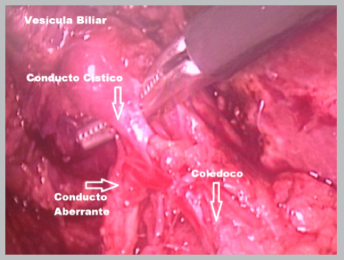

Se programó una colecistectomía laparoscópica, durante la cual se encontró como hallazgos una vesícula de paredes gruesas, distendida, de 7x4x3 cm de diámetro, emplastronada con epiplón; conducto cístico fino y corto; y se evidenció la presencia de un conducto del segmento VI anómalo con terminación a nivel del conducto cístico; foto 2. No se presentaron complicaciones durante la cirugía y la evolución post- quirúrgica fue favorable. Se realizó una colangioresonancia de control dos semanas después de la cirugía, la cual demostró un conducto hepático funcional que drenaba el segmento hepático VI; foto 3.

Foto 2 Colecistectomía laparoscópica. se observa una vesícula distendida; conducto cístico fino y corto; y la presencia de un conducto del segmento VI anómalo con terminación a nivel del conducto cístico.